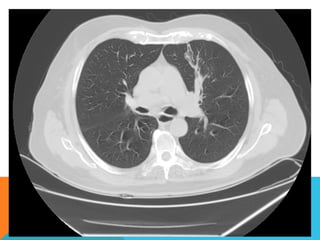

Ambos pulmones con neumatización conservada, con sobredistensión pulmonar, y áreas de atrapamiento aéreo,

bilateral con cambios fibrosos cicatriciales apicales derechos. Se demuestran áreas de condensación en topografía

predominantemente parenquimatosa pulmonar derecha, la mayor de ellas evidenciada hacia la base, acompañada

de broncograma aéreo, la medición máxima al corte axial de 6.1 por 2.2 cm, en topografía del segmento posterior

del lóbulo inferior, S10 así como también otra más se definen topografía de similares características en topografía

del segmento medial del lóbulo medio, S5. En topografía parenquimatosa pulmonar izquierda imagen de similares

características a las ya descritas en topografía del segmento lingular inferior, S4.

No hay derrame ni áreas de engrosamiento pleurales.

ABORDAJE TÉCNICO: Serealiza estudio con ventana mediastinal y de parénquima pulmonar con técnica de ALTA RESOLUCION, en inspiración y espiración, mediante  cortes axiales, desde ápices hasta bases pulmonares, con las siguientes observaciones En las partes blandas y las estructuras óseas dentro de los límites de la normalidad. Las regiones axilares libres. Ambos pulmones con neumatización conservada, con sobredistensión pulmonar, y áreas de atrapamiento aéreo, bilateral con cambios fibrosos cicatriciales apicales derechos. Se demuestran áreas de condensación en topografía predominantemente parenquimatosa pulmonar derecha, la mayor de ellas evidenciada hacia la base, acompañada de broncograma aéreo, la medición máxima al corte axial de 6.1 por 2.2 cm, en topografía del segmento posterior del lóbulo inferior, S10 así como también otra más se definen topografía de similares características en topografía del segmento medial del lóbulo medio, S5. En topografía parenquimatosa pulmonar izquierda imagen de similares características a las ya descritas en topografía del segmento lingular inferior, S4. No hay derrame ni áreas de engrosamiento pleurales. El patrón vascular es de características normales donde no se delimitan imágenes de lesiones aneurismáticas únicamente cambios por aortoesclerosis incipiente. El corazón de dimensiones conservada, de contornos regulares, sin desplazamientos; en la región hiliar derecha se define adenopatía de medición máxima corte axial de 1.6 por 1.4 cm.

En los cortesrealizados hacia las bases pulmonares es posible delimitar los órganos sólidos intraabdominales tales como el hígado sin anormalidades que consignar; se demuestra imagen hiperdensa puntiforme en topografía del parénquima esplénico en relación a calcificación inespecífica. Hay distensión aérea esofágica que lo define prácticamente su totalidad. Se demuestran imágenes hiperdensas en topografía intraluminal vesicular que corresponden con colelitiasis. Se define imagen hipodensa parenquimatosa renal superior derecha con patrón de atenuación homogéneo, líquido que condiciona la sospecha de lesión focal benigna tipo quística simple. INTERPRETACIÓN DIAGNÓSTICA:   ESTUDIO ANORMAL QUE DEMUESTRA HALLAZGO INESPECIFICO DE SOBREDISTENSIÓN PULMONAR  CON CAMBIOS FIBROSOS CICATRICIALES APICALES DERECHOS Y ÁREAS DE CONDENSACIÓN PARENQUIMATOSAS PULMONARES, DE PREDOMINIO DERECHO, LA DE MAYORES DIMENSIONES BASAL DERECHA, ASOCIADA CON BRONCOGRAMA AÉREO. COLELITIASIS.

El estudio radiológicosimple evidencia una lesión nodular menor del centímetro, radiodensa, caracterizada como granuloma cálcico. En mi opinión el estudio de TCAR fue realizado por ese motivo y ello permito identificar los hallazgos “floridos” que ya se señalan y se muestran en las imagen axiales ya seleccionadas.